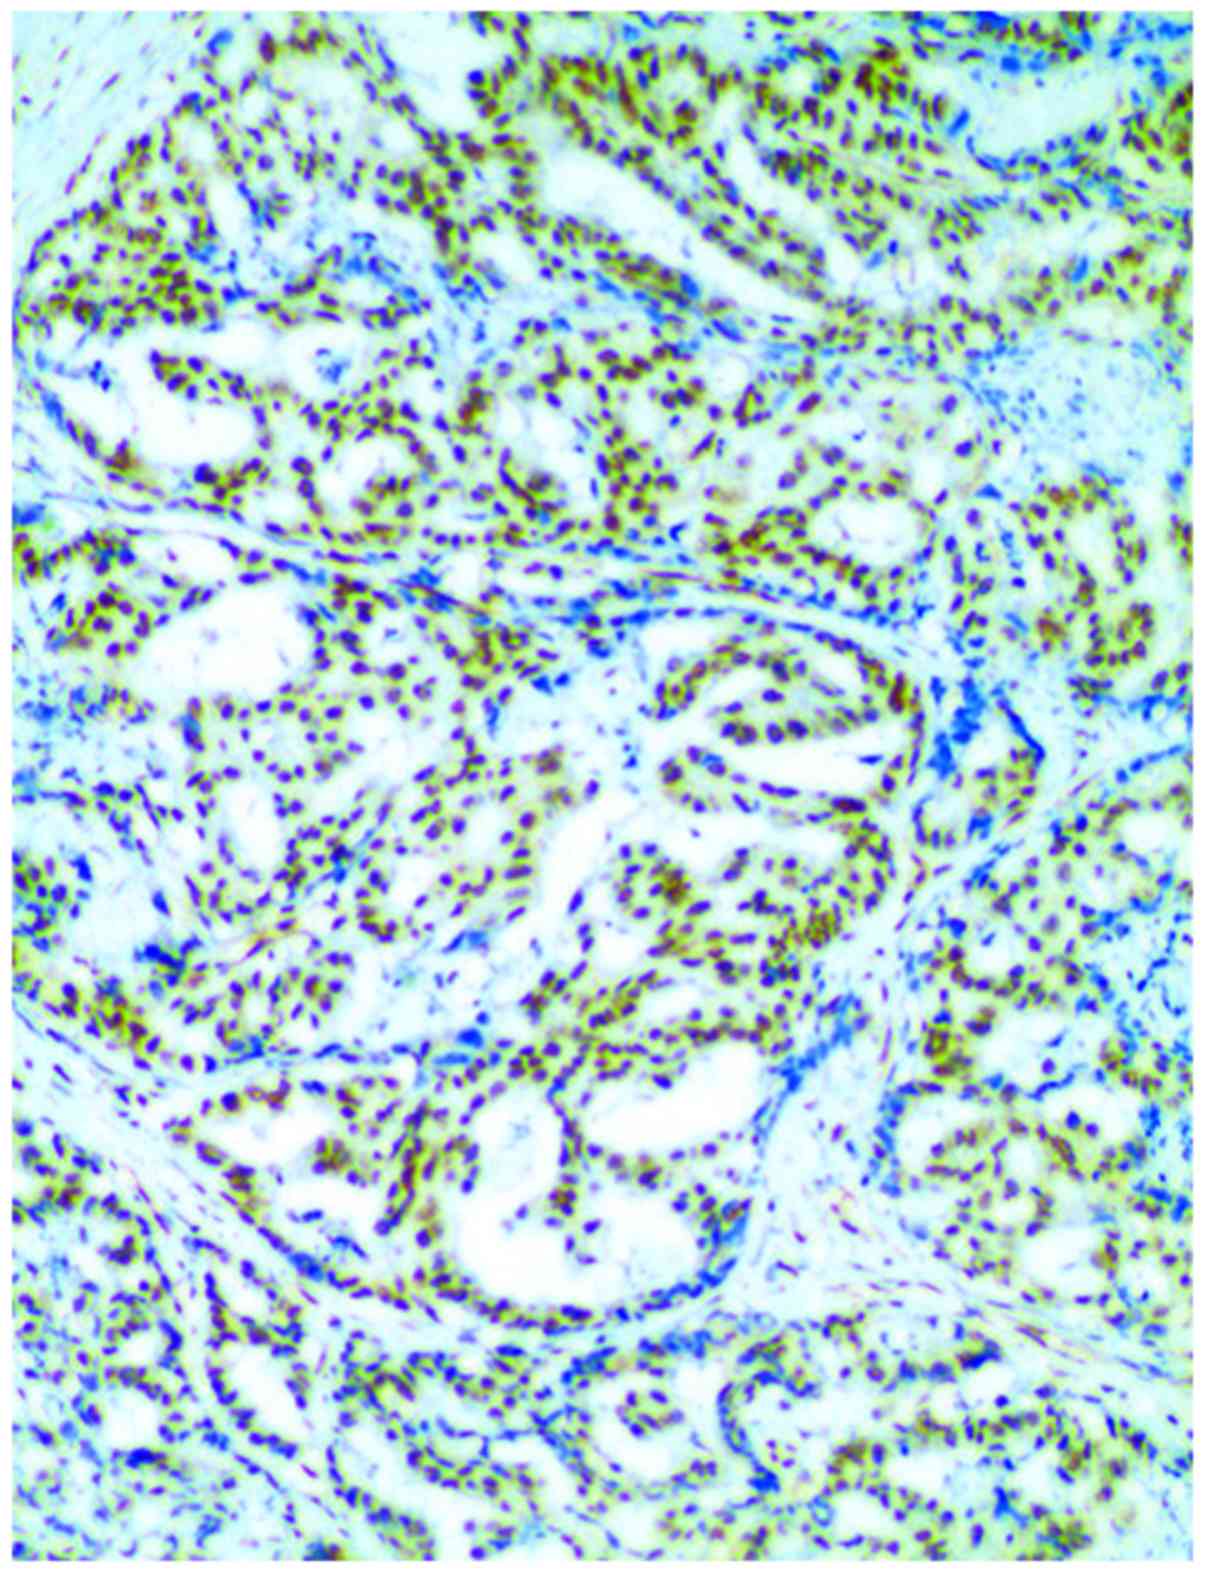

In comparison of XPF expression, we found that the

significance (P<0.05) (Table II

and Fig. 1).